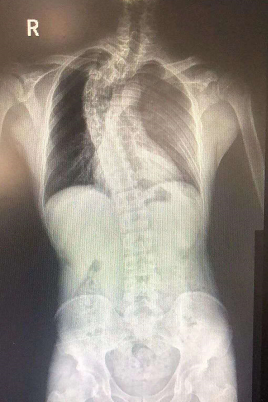

7月23号,已经大学毕业的张强,在老师的帮助下,被爱心组织送到了贵航三〇〇医院接受治疗。彭建兴主任医师告诉记者,一般特发性脊柱侧弯小于20度,可以通过注意平时的姿势和针对性锻炼进行矫正,而张强的脊柱后凸侧弯畸形严重,已经大于50度,心肺因受压迫导致心肺功能明显降低,属于极重度脊柱侧弯。手术还有瘫痪,大出血,术后感染的风险等风险,手术难度非常大。

8月7号,经过6个多小时的手术,张强弯曲的脊柱得以矫正恢复。彭医生说张强的术后恢复愈合非常好,神经功能,呼吸功能都比以前顺畅多了。身高可以增长4~5公分。最主要是矫型之后,脊椎不受压了,心肺功能不受影响。彭医生说,现在张强最大的变化就是脸上有了笑容。